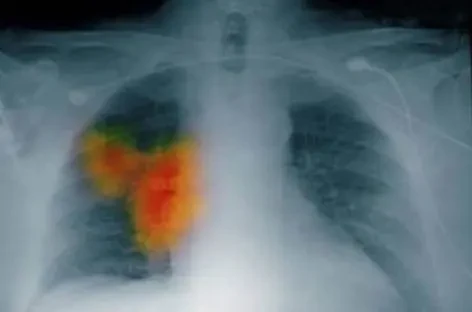

但實際上,肺癌這個 「狡猾的敵人」,它發出的第一個信號往往藏在一些細微之處,悄無聲息地潛伏在身體里,很多人就這樣在渾然不覺中錯過了最佳治療時機。

然而,很多肺癌患者在早期根本沒有這些 「典型表現」。

醫學研究數據顯示,超過 70% 的肺癌患者在確診時,已經出現了上述這些症狀。

肺癌的早期症狀和腫瘤的大小、位置關係密切。